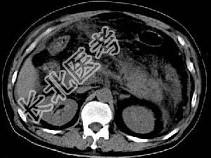

- 单项选择题根据所提供的图像,最可能的诊断是 ( )

A、胰腺癌

B、急性胰腺炎

C、慢性胰腺炎

D、正常胰腺

E、以上都不是